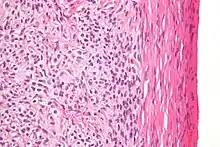

High magnification micrograph of a thecoma. H&E stain.

Microscopically, the tumour cells have abundant lipid-filled cytoplasm.